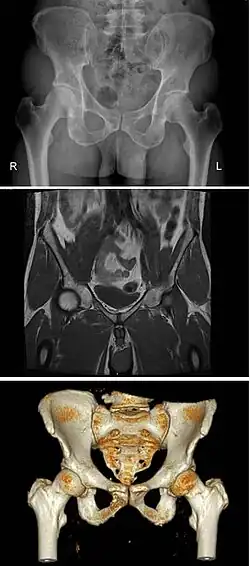

Diameters of pelvic inlet